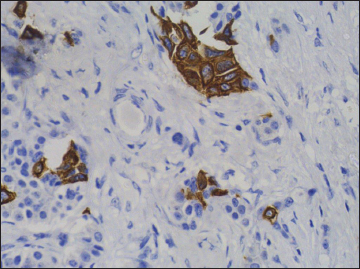

| Figure 9 Immunohistochemistry on subcarinal node showing strong positivity for synaptophysin